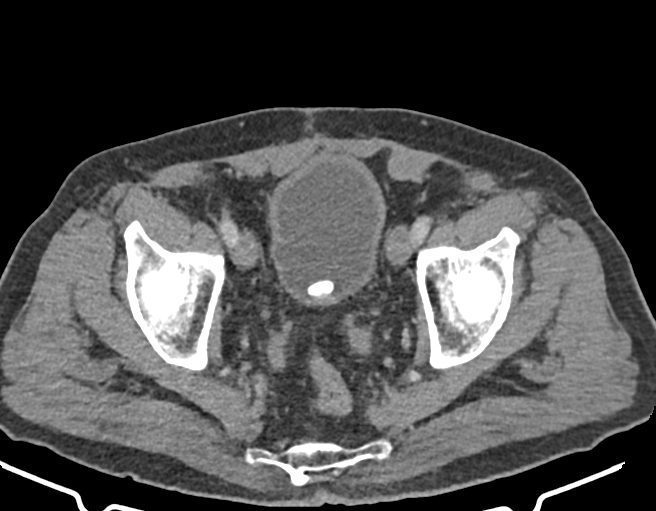

– سنگ 13 mm در مثانه

– چربي در کانال اينگوينال راست مطرح کننده هرني

– هيپرلوردوز لومبوساکرال، اسکوليوزيس توراکولومبار و spondylolysis دوطرفه L5 همراه با تغييرات DJD به ويژه در ناحيه توراکولومبار مشهود است .